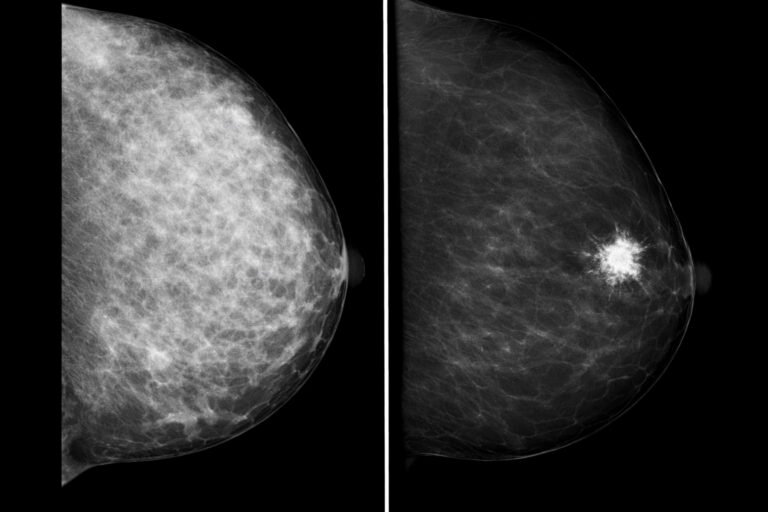

- Distorsione architetturale (mammografia/tomosintesi): non è un “nodulo tondo”, ma un’alterazione delle linee del tessuto.

- Densità mammaria (seno denso): in un seno molto ghiandolare, la mammografia può essere meno sensibile; per questo spesso si integra con ecografia. Trovi un approfondimento qui.

Mammografia / Tomosintesi

- ✅ Fondamentale soprattutto dai 40 anni e per reperti come microcalcificazioni o distorsioni.

- ⚠️ Usa radiazioni, ma con dosi basse: nel contesto diagnostico, il beneficio supera nettamente il rischio.

- ⚠️ Nei seni densi può “vedere meno”, per questo spesso si integra con eco.